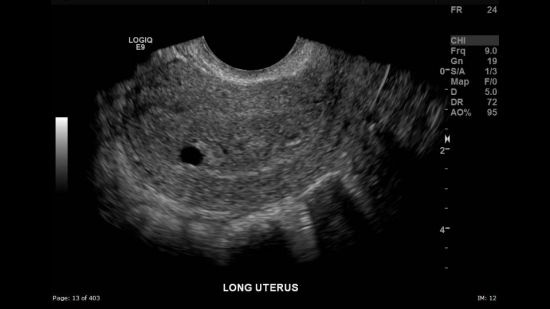

můžete mi prosím sdělit, co je to gestační váček v děloze?

Dnes jsem byla na gynek.prohlídce na podezření těhotenství (páč mám podezření už asi měsíc a půl) a prý těhotná nejsem, ale ten gestační váček přesně stejně velký jsem měla taky, akorát vpravo, pak mi ukazovala dělohu.. Kamarádka říkala, že když byla těhotná, tak ho v děloze měla a když ne, tak tam nic nebylo. Krev mi gyn.nevzala.

Znamená to něco tedy? Jsem z toho blázen. Gyn.mi vysvětlovala, kde je děloha,atd...i ten váček mi ukazovala.